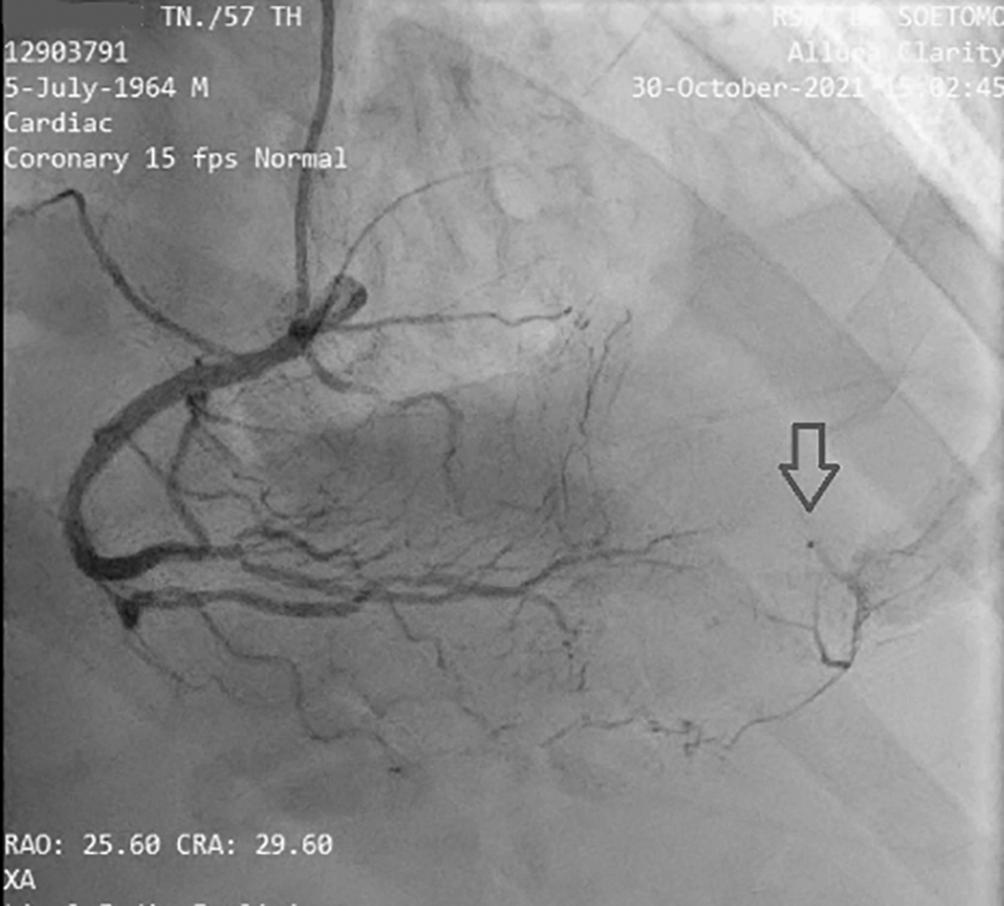

Before the invasive strategy was done, the patient had another ECG eight hours after the first ECG, based on the second (Figure 2). The ECG showed ST-segment elevation changes that were greater than 1 mm. The early invasive strategy (Figure 3 and Figure 4; Extended data: Video 1 and Video 2)3,4 showed that the left anterior descending artery (LAD) had total occlusion of 100% in the middle LAD (Figure 3). The left circumflex artery (LCx) had non-significant stenosis of 40% proximal and 65% distal, and right coronary artery (RCA) had non-significant stenosis of 55% distal. The RCA had grade 2 collateral arteries that supply blood to the mid LAD (Figure 4).

The collateral of the coronary artery is classified into five grades. Collateral grade 0 reveals no flow between the collateral of the coronary artery. This condition can occur when several collateral arteries are visible yet not angiographically apparent at any other time. Collateral grade 1 flow reveals a barely apparent collateral coronary artery. Sometimes, there might be an unclear connection with the significant epicardial coronary artery. Collateral grade 2 flow reveals a moderately opaque collateral coronary artery but it was only present through 75% of the cardiac cycle. Collateral grade 3 flow reflects a well-opacified collateral coronary artery while the column of dye is well defined (i.e., >0.5 mm in diameter), but it was <0.7 mm wide throughout most of its length. Collateral grade 4 flow mimics collateral grade 3. The collateral is very well opacified, fills antegrade, and is very large. It was >0.7 mm in diameter throughout its length.12,13

The cardiac catheterization results found that a collateral artery originating from the right coronary artery (RCA) supplied the mid-distal LAD. Therefore the heart muscle that should have been severely damaged due to not getting blood supply from the LAD could still survive due to the presence of the collateral artery. Previous data has established that enough collaterals can prevent ischemia and directly induce spontaneous reperfusion in one-third of NSTE-ACS patients. Spontaneous reperfusion with well-developed coronary collateral circulation is associated with a better prognosis in cardiovascular mortality reduction.14